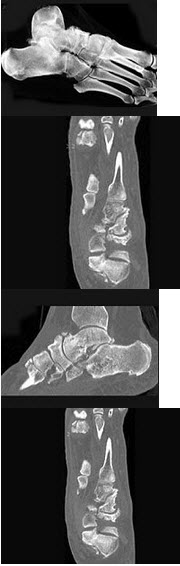

15、单项选择题

女,27岁,有外伤史,结合图像,最可能的诊断是()

A.骨斑点症

B.骨梗死

C.骨岛

D.皮肤骨膜肥厚症

E.石骨症